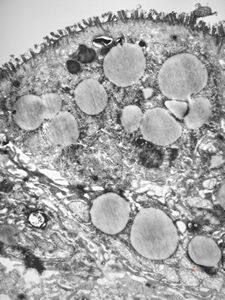

M,35y. | duodenum … lipid malabsorption - susp. hypo-beta-lipoproteinemia